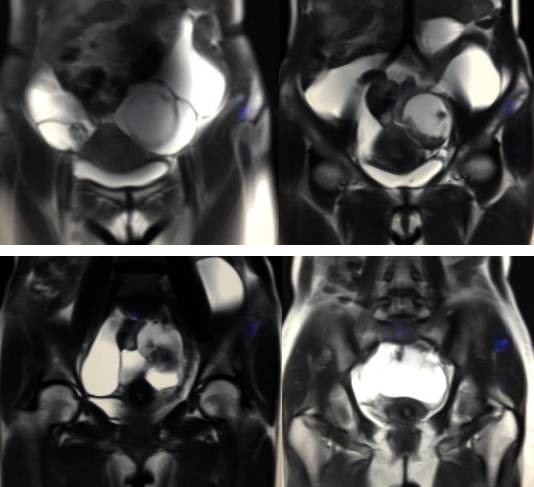

MR检查:

病理结果:黄体血肿

黄体血肿为正常排卵过程中,卵泡层破裂,引起出血,较多的血液潴留在卵泡或黄体腔内形成血肿。

正常黄体直径为15mm左右,以后转变为白体,并在下一个周期的卵泡期自然消退。若黄体内出血量较多,则形成黄体血肿,或称黄体内出血,出血性黄体。黄体血肿多为单侧,一般直径为40mm,偶可达100mm,黄体血肿被吸收后可导致黄体囊肿,较大的血肿破裂时可出现腹腔内出血,剧烈腹痛、少量阴道流血和腹膜刺激征,不易与宫外孕区别。

黄体血肿早期:囊内出血较多时,表现为卵巢内近圆形囊肿,囊壁厚,内壁粗糙。

黄体血肿中期:黄体血肿内血液凝固,部分吸收,囊壁变薄而,内壁光滑。

黄体血肿晚期:血液吸收后囊肿变小,转变为白体,内部回声呈实性稍高回

声,与周围卵巢组织分界不清,面靠彩超显示其周围环状血流判断,当血液完全吸收后形成黄体囊肿,囊壁变得光滑,与卵巢其他囊肿难以区分。

根据时间不同MR信号也有所不同,TIWI脂肪抑制序列可以鉴别脂肪和出血。